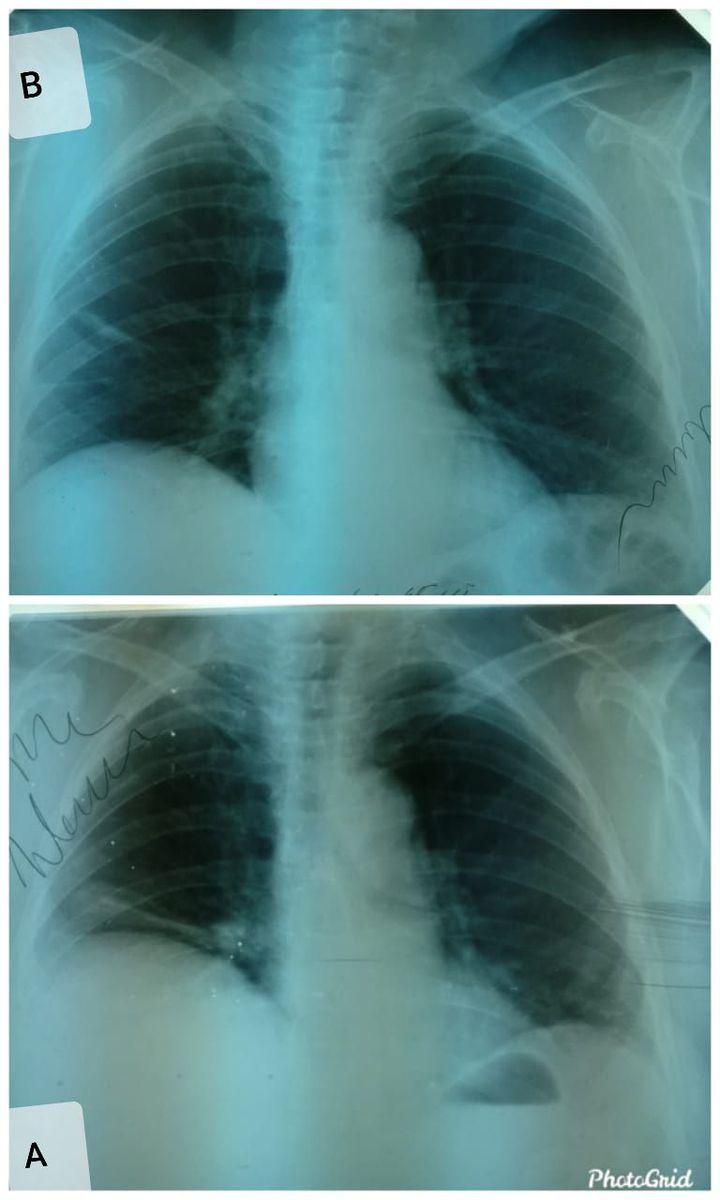

A 65 years old female was hospitalized with the symptoms of lobar pneumonia, the X ray was seen with a very interesting picture with an uplift of diaphragm (panel A). The patient was treated with antibiotics the treatment was also followed with detoxification and oxygen therapy and after 2 weeks fluroscopy was done again and the another picture (panel B), the infiltration reduced, the diaphragm was also in position and the lung picture came to normal